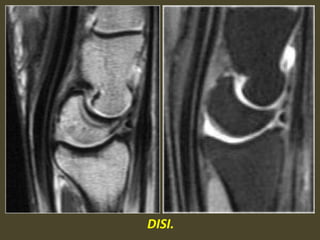

A simple approach is to consider the lunate

which is usually the easiest carpal bone to

visualize on a lateral wrist image. If the

lunate is abnormally tilted in a dorsal

direction on a standard lateral wrist image,

a DISI should be considered. If the lunate is

abnormally tilted in a volar direction a VISI

should be considered. DISI is due to

disruption of the scapho-lunate articulation.

VISI is secondary to disruption of the luno-

triquetral articulation.

DISI deformity.

DISI.